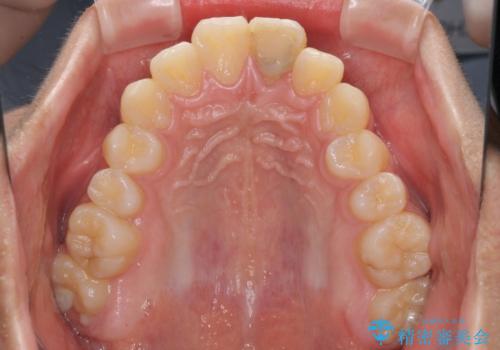

膨らんだ口元 ワイヤー装置での抜歯矯正

上下前歯が著しく前突している状態であったので、上下左右の第1小臼歯4本を抜歯し、ワイヤー装置にて矯正治療を行うこととしました。

小学生の頃に上顎前歯をぶつけ、歯の一部が破損している状態であったので、歯根が歯槽骨と癒着して移動しない可能性がありましたが、無事に治療を終えることができました。